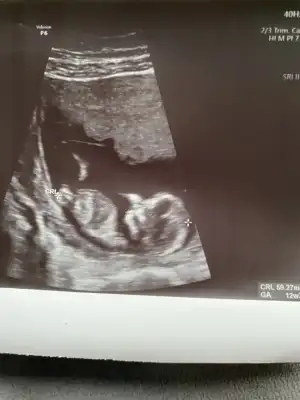

Az önce dr dan geldim. Bana kız dedi ya 17hafta olduk. 12.haftada da kiz demisti. Tum belirtilerim erkekti amaErkek görünüyor![]()

Evet bu sefer de kız dedi kesin konuştu ama ben 20. Hafta detaylıyı beklecepim emin olmak için. Teşekkür eserimKız gibi sanki daha önceki karanlık USG emin olmamıştım

En iyi 11 12 13 haftalar olmalı şimdilik kız yönünde ama yanıltabilirIkra meyra bana da yorum yapar mısın cinsiyet için